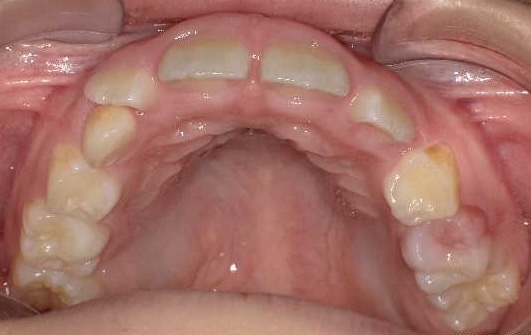

矯正後

| 症状 | 上顎前突 過蓋咬合 |

| 通院目的 | 永久歯を抜かずに歯並びを治したい。 |

| 処置内容 | プレート拡大処置・ディスタライザー・インビザライン・オーソテイン・マルチブラケット装置 |